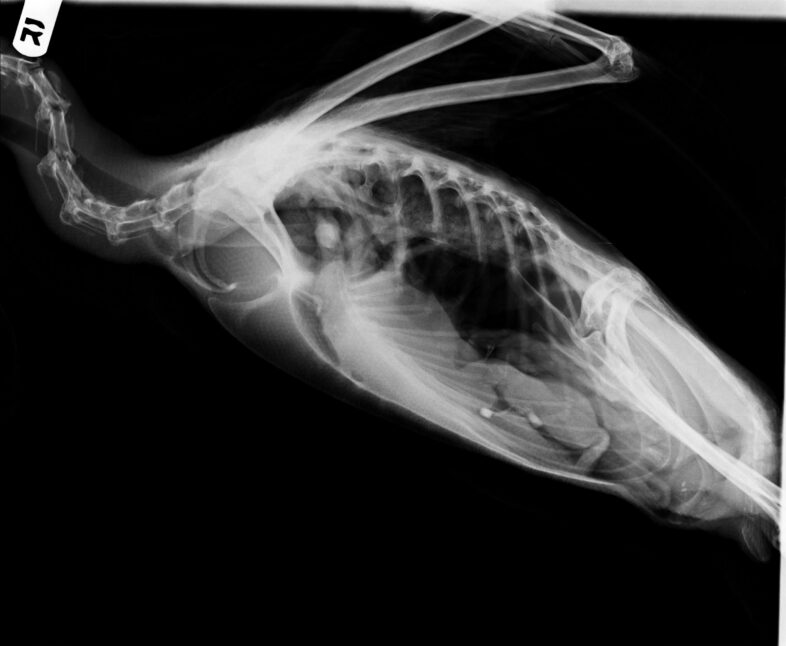

The loon’s x-ray revealed some evidence of blunt trauma to the bird’s chest; however, the experts couldn’t identify any obvious injuries. © Provided by VINS staff

Although the images yielded no smoking guns, there were potential indications of blunt injury to the chest area, suggesting that the conflict with the other loons may have turned to violence at some point. Other causes of such injury could be a crash landing (such as landing on a surface other than water) or a boat collision.

The next significant finding was a high level of lead in the blood, but no obvious lead object in the x-ray. Had a sinker been ingested and then passed through the gizzard and GI tract? Lead sinkers weighing one-half ounce or less have been illegal in Vermont since 2007, but people still legally use larger lead sinkers and jigs, and many anglers still have lead tackle in their boxes. Notably, in the decade that followed Vermont’s lead tackle ban in 2007, we observed a three-fold decrease in loon mortalities from lead. But between 2019 and 2023, twelve loons have died from lead poisoning after ingesting fishing gear—a major increase. We don’t know why, but to try to stem the tide VCE teamed up with the Vermont Fish & Wildlife Department to launch the Vermont Fish Lead Free project. We have installed lead tackle (and fishing line) collection tubes at nearly 30 fishing access points statewide.